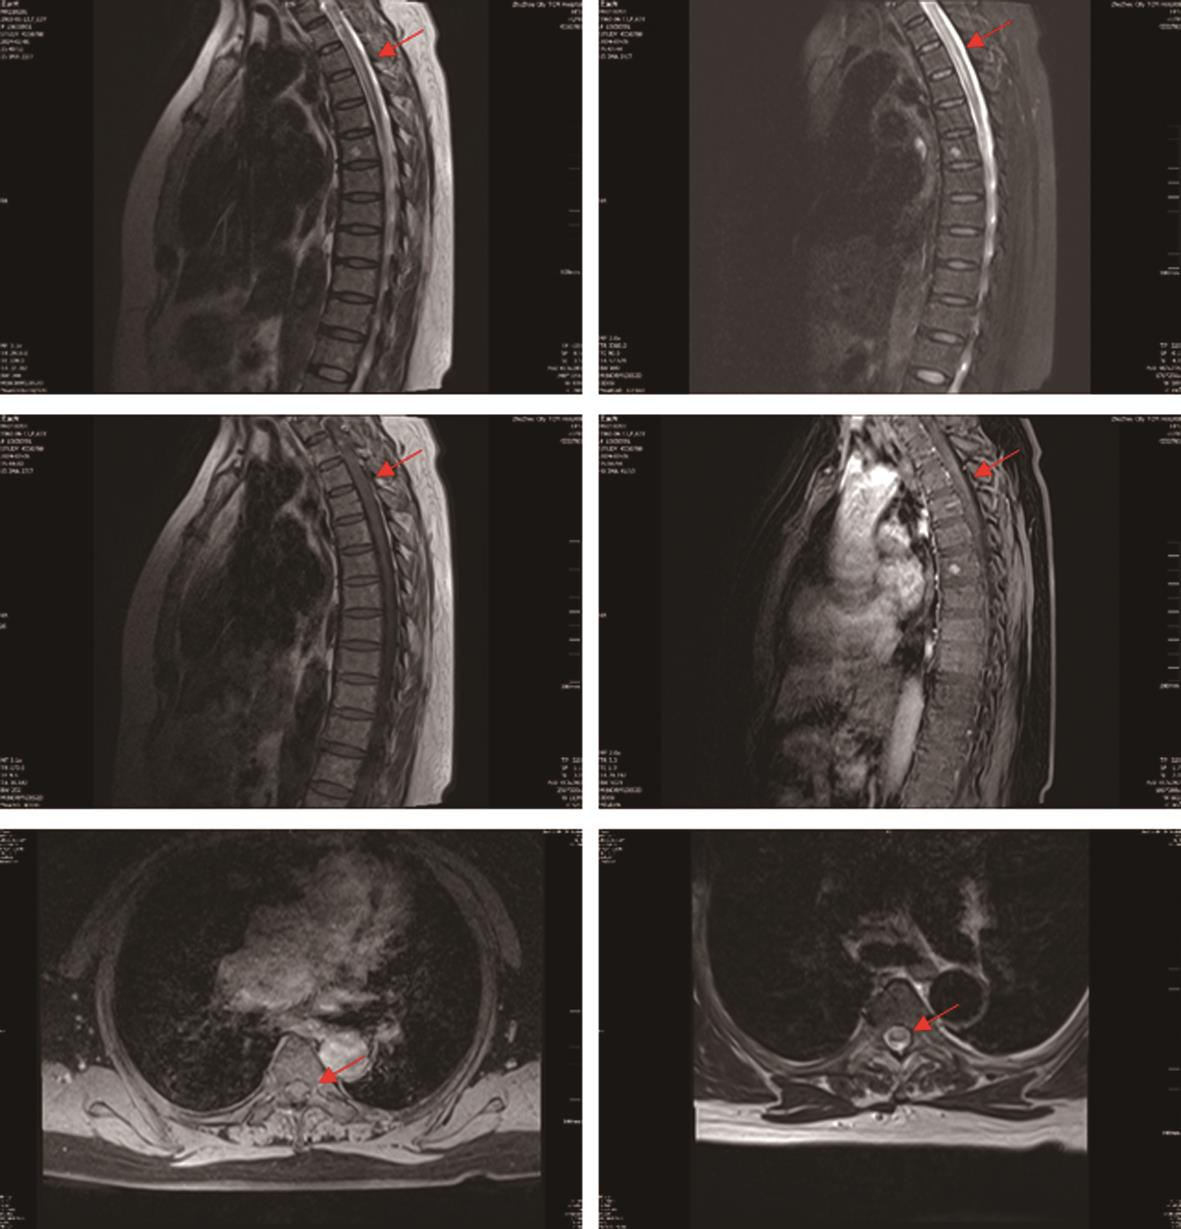

摘要:该文报道了系统性红斑狼疮(SLE)、可能抗磷脂综合征(APS)与视神经脊髓炎谱系疾病(NMOSD)在同一患者体内的重叠表现,并探讨三者可能的关联机制。患者,女性,57岁,病程可分为3个阶段:第一阶段表现为反复血小板减少,伴高滴度抗心磷脂抗体阳性;第二阶段出现双眼视力进行性下降直至失明,眼底检查可见双眼视神经萎缩,视神经磁共振成像(MRI)及脊髓MRI提示脱髓鞘病变;第三阶段则表现为双下肢麻木、皮肤瘀点及多系统受累,免疫学检查证实抗核抗体、抗双链DNA抗体及抗SSA抗体阳性。患者最终确诊为SLE合并可能APS及双阴性NMOSD。该病例显示SLE、APS及NMOSD可能通过免疫紊乱与血管损伤机制相互交织,共同促进疾病的发生发展。临床实践中,对于病程复杂且表现多样的患者,应警惕多种自身免疫病的重叠,结合临床表现、免疫学指标及影像学检查,进行全面评估和早期干预,可能有助于改善长期预后。